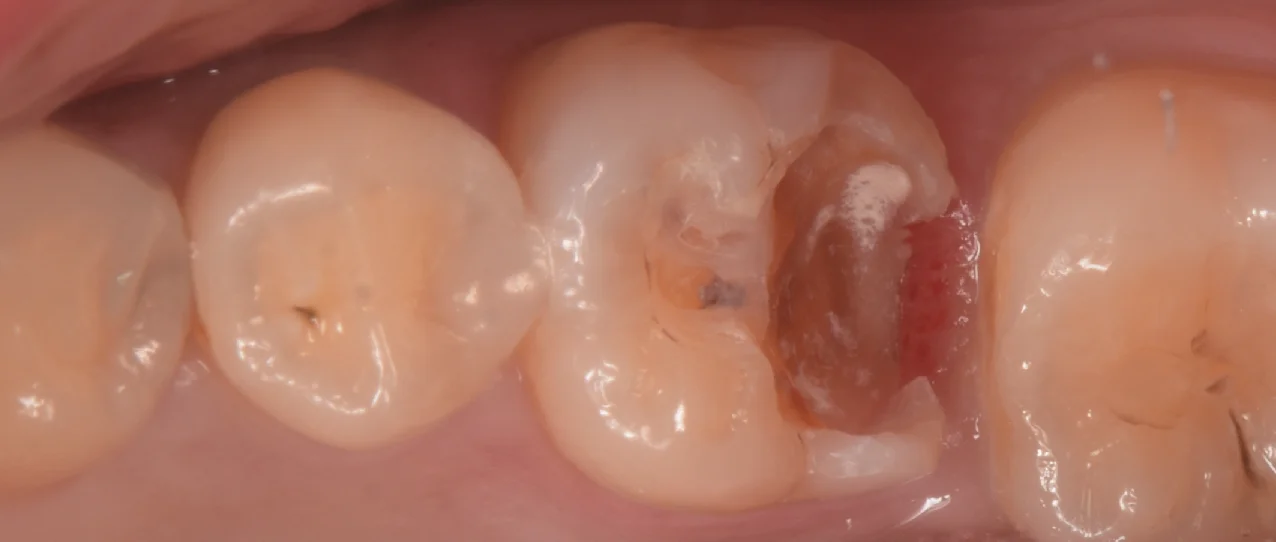

虫歯を取り切ったのがこちらになります。

歯科医師の方のCAD/CAMインレーを治療。|坂寄歯科医院(取手市藤代) - 画像3

今回は自費診療ですが、歯茎よりも深すぎる位置まで歯がなくなってしまっていたため、私の技術力でそこに綺麗にラバーダムを行うのが困難と判断し、そのまま他の器具で乾燥状態をしっかりと持続させなら充填していきました。